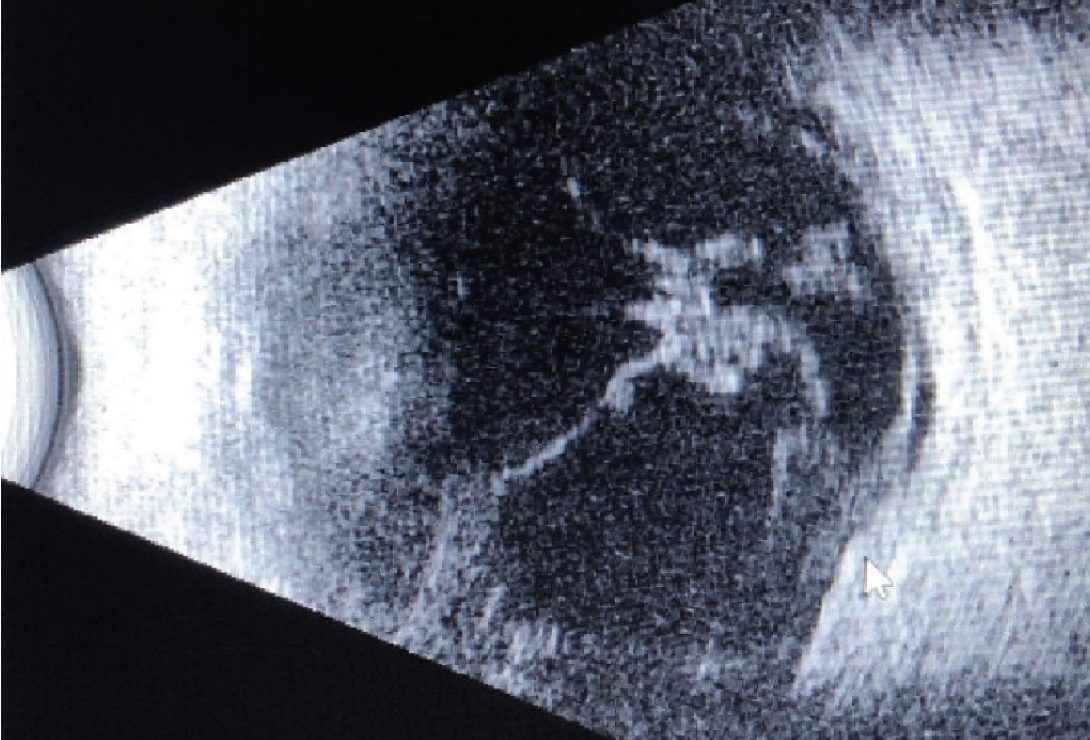

Read moreDetailsPresentación del caso: En esta ocasión, presentamos el caso de una mujer de 54 años que...